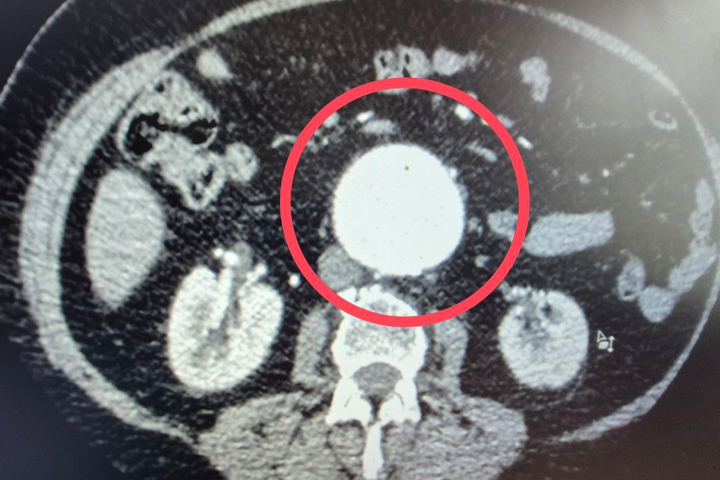

Как пояснили медики, к ним поступила 60-летняя пациентка с крайне опасным диагнозом — мешотчатая аневризма брюшной аорты.

«Это патологическое расширение главного сосуда организма, которое в любой момент может привести к внутреннему кровотечению. Случай действительно уникальный — аневризма брюшной аорты считается «бомбой замедленного действия», а мешотчатая форма особенно опасна из-за риска мгновенного разрыва.

Ситуация была настолько серьезной, что в проведении операции женщине отказали даже в областных клиниках», — пояснили в больнице.